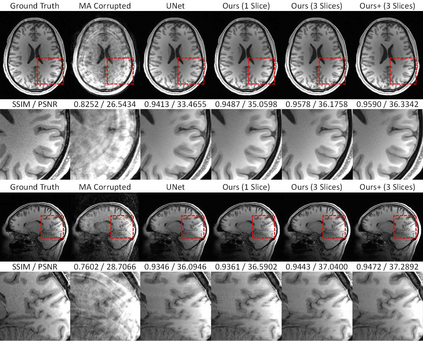

Shortening acquisition time and reducing the motion artifacts are two of the most essential concerns in magnetic resonance imaging. As a promising solution, deep learning-based high-quality MR image restoration has been investigated to generate highly-resolved and motion artifact-free MR images from lower resolution images acquired with shortened acquisition time or motion artifact-corrupted images. However, numerous problems still exist to prevent deep learning approaches from becoming practical in the clinic environment. Specifically, most of the prior works focus solely on the network but ignore the impact of various down-sampling strategies on the acquisition time. Besides, the long inference time and high GPU consumption are also the bottlenecks to deploy most of the prior works in clinics. Furthermore, prior studies employ random movement in retrospective motion artifact generation, resulting in uncontrollable severity of motion artifact. More importantly, doctors are unsure whether the generated MR images are trustworthy, making diagnosis difficult. To overcome all these problems, we adopted a unified framework of 2D deep learning neural network for both 3D MRI super-resolution and motion artifact reduction, demonstrating such a framework can achieve better performance in 3D MRI restoration tasks compared to other state-of-the-art methods and remain the GPU consumption and inference time significantly low, thus easier to deploy. We also analyzed several down-sampling strategies based on the acceleration factor, including multiple combinations of in-plane and through-plane down-sampling, and developed a controllable and quantifiable motion artifact generation method. At last, the pixel-wise uncertainty was calculated and used to estimate the accuracy of the generated image, providing additional information for a reliable diagnosis.